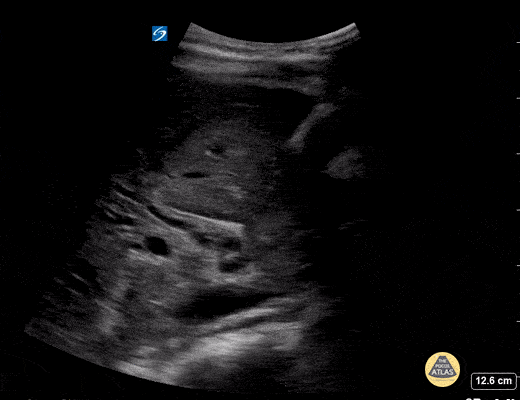

11 year old female with abd pain and emesis. Kicked in stomach by horse 6 weeks prior with grade 4 liver lac. Seen a few days ago with reassuring labs and US. Now with rising aminases and bilirubin. POCUS demonstrated a dilated and edematous gallbladder with sludge, and a dilated CBD and the classic 'double barrel' sign. Contributed by: Matthew Moake, MD PhD